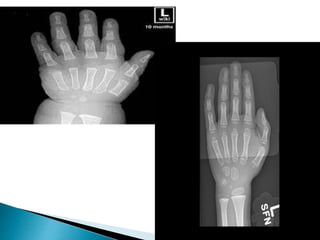

 Disappearance(closure) of this plate occurs at

different time in different bone and this is

important is identifying bone age.

 Primary centersappear in the diaphysis before birth  Secondary centers appear later in life in the epiphysis.  In the secondary ossification centers, cartilage remains in two regions: ◦ the articular cartilage ◦ the epiphyseal cartilage ( epiphyseal plate or growth plate) 

• 54.

 The epiphysealcartilage is responsible for the growth in length of the bone and disappears in adults.  Disappearance(closure) of this plate occurs at different time in different bone and this is important is identifying bone age.